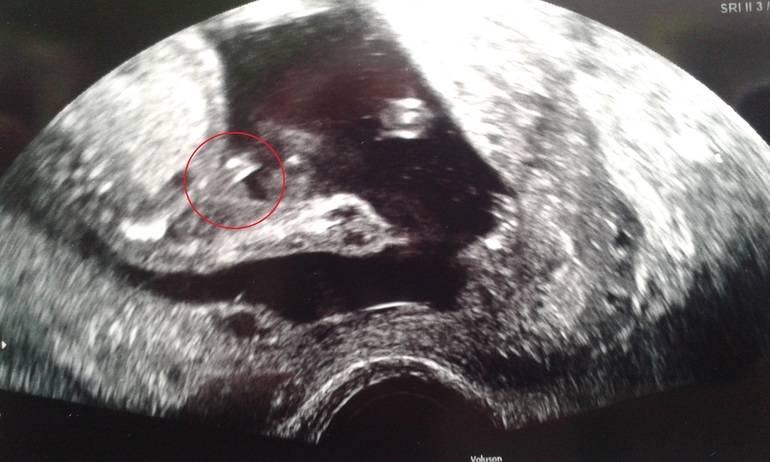

Пол малышаЛицо.

Кто 3 раза была и не одного точного ответа.Ездила в последний раз в Ишим , есть опытная Узист Сокотова.Она в 13 н. пол определяет.Я два раза попала к другой женщине, а в последний раз вообще все в отпуске и был молодой парень.Учитывая что он пересматривал..и не уверенно ответил, не дал 100%.Сказал ещё лучше прийти.)

Гов. не торчит)) похоже на девочку.А как же мошонка??? Во сколько опускаются яички???

Помоему в 20-22 н, а может и позже.Да всё может быть!Между ног хозяйство зажато.Но я не буду тянуть с УЗИ до 32 н., скорее поеду на свой ДР к Сокотовой.(как раз 30 н. будет).